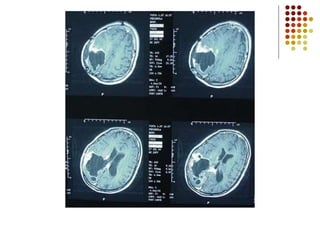

Ejemplos de Tumores

Cerebral